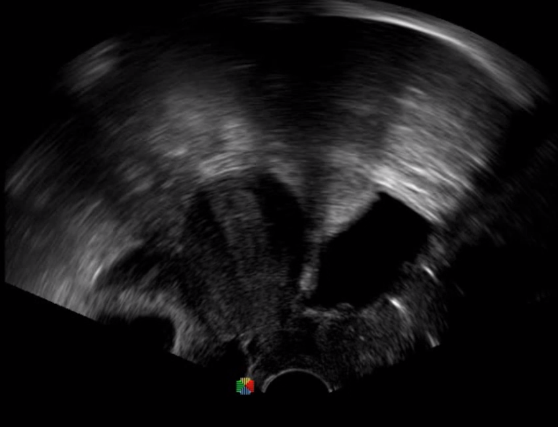

腹腔鏡超聲是超聲技術(shù)和腹腔鏡技術(shù)的融合,腹腔鏡超聲降低了對(duì)超聲探測(cè)深度的要求。由微小切口進(jìn)入手術(shù)部位,多角度彎曲可選擇,降低手術(shù)難度及風(fēng)險(xiǎn);與受檢組織器官直接接觸,有效避免氣體干擾。

應(yīng)用科室:麻醉科、手術(shù)室、普外科、泌尿外科、婦產(chǎn)科、腫瘤科、介入科等

腹腔鏡下 肝臟占位